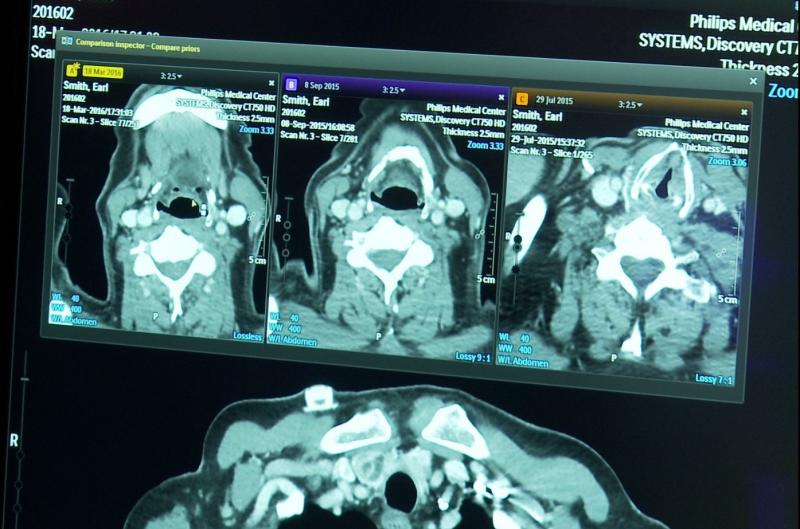

In contrast to the specific objectives of Infervision products, Israeli startup Aidoc Medical is building algorithms to distinguish between abnormal and normal images. Its analyses would be used to prioritize cases according to the likelihood of disease.

“We have created an architecture that captures a wide array of different types of pathology that would be of interest to the radiologist,” said Tom Valent, Aidoc vice president of business development. “By doing that, we believe we can really improve the workflow — not by cherry picking a few pathologies, but by giving a wide perspective.”

Valent said analyses using Aidoc algorithms will give radiologists a “preview” of images that urgently require interpretation. “Our AI highlights the abnormal cases and, by doing that, we enable the radiologist to prioritize the cases and to read those cases earlier than he would otherwise.”